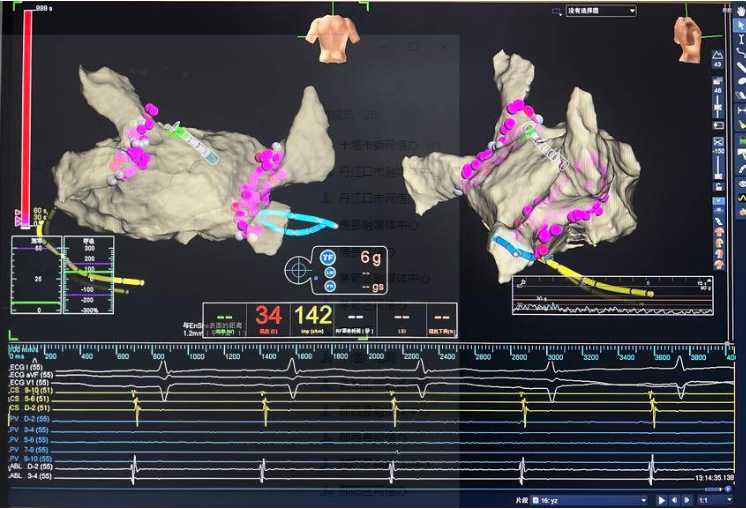

消融图片

手术当日,范群雄副主任医师、赵继先主任医师领衔的手术团队严阵以待。此次手术,穿刺环节是关键和难点。由于卵圆孔封堵器的存在,穿刺路径受到了极大的限制。为了克服这一困难,手术团队采取了多项措施,确保手术安全、顺利。首先,他们利用DSA(数字减影血管造影)和三维心脏建模技术,对朱女士的心脏结构进行了精确的分析,使得手术团队能够清晰地看到房间隔、卵圆孔封堵器以及周围血管的位置关系,从而制定出更加精准的穿刺路径。其次,手术团队在穿刺过程中,小心翼翼地操控穿刺针,通过精准把控力度和角度,在复杂的心脏结构中准确地找到穿刺点,并避免对周围组织的损伤。

随后,手术团队乘胜追击,运用射频消融技术进行了双侧肺静脉前庭及上腔静脉电隔离,精准地消除了房颤病灶,恢复了心脏的正常节律。紧接着,手术团队将左心耳封堵器放置到位,钩挂稳定。造影显示,左心耳封堵完好,未见明显残余漏。这一步骤的成功,彻底阻断了血栓形成的源头,为朱女士的未来生活提供了有力的保障。